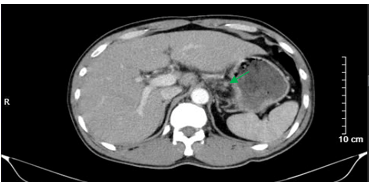

Hình 4. Hình ảnh chụp cắt lớp vi tính ổ bụng. Hình ảnh dày thành hang vị dạ dày, mất cấu trúc lớp, bề dày khoảng 10mm, sau tiêm ngấm thuốc (vòng tròn màu vàng)

Hình 5. Hình ảnh chụp cắt lớp vi tính ổ bụng. Hình ảnh vài hạch nhỏ cạnh bờ cong nhỏ dạ dày, sau tiêm ngấm thuốc, kích thước giảm so với trước điều trị tân bổ trợ (mũi tên màu xanh lá)